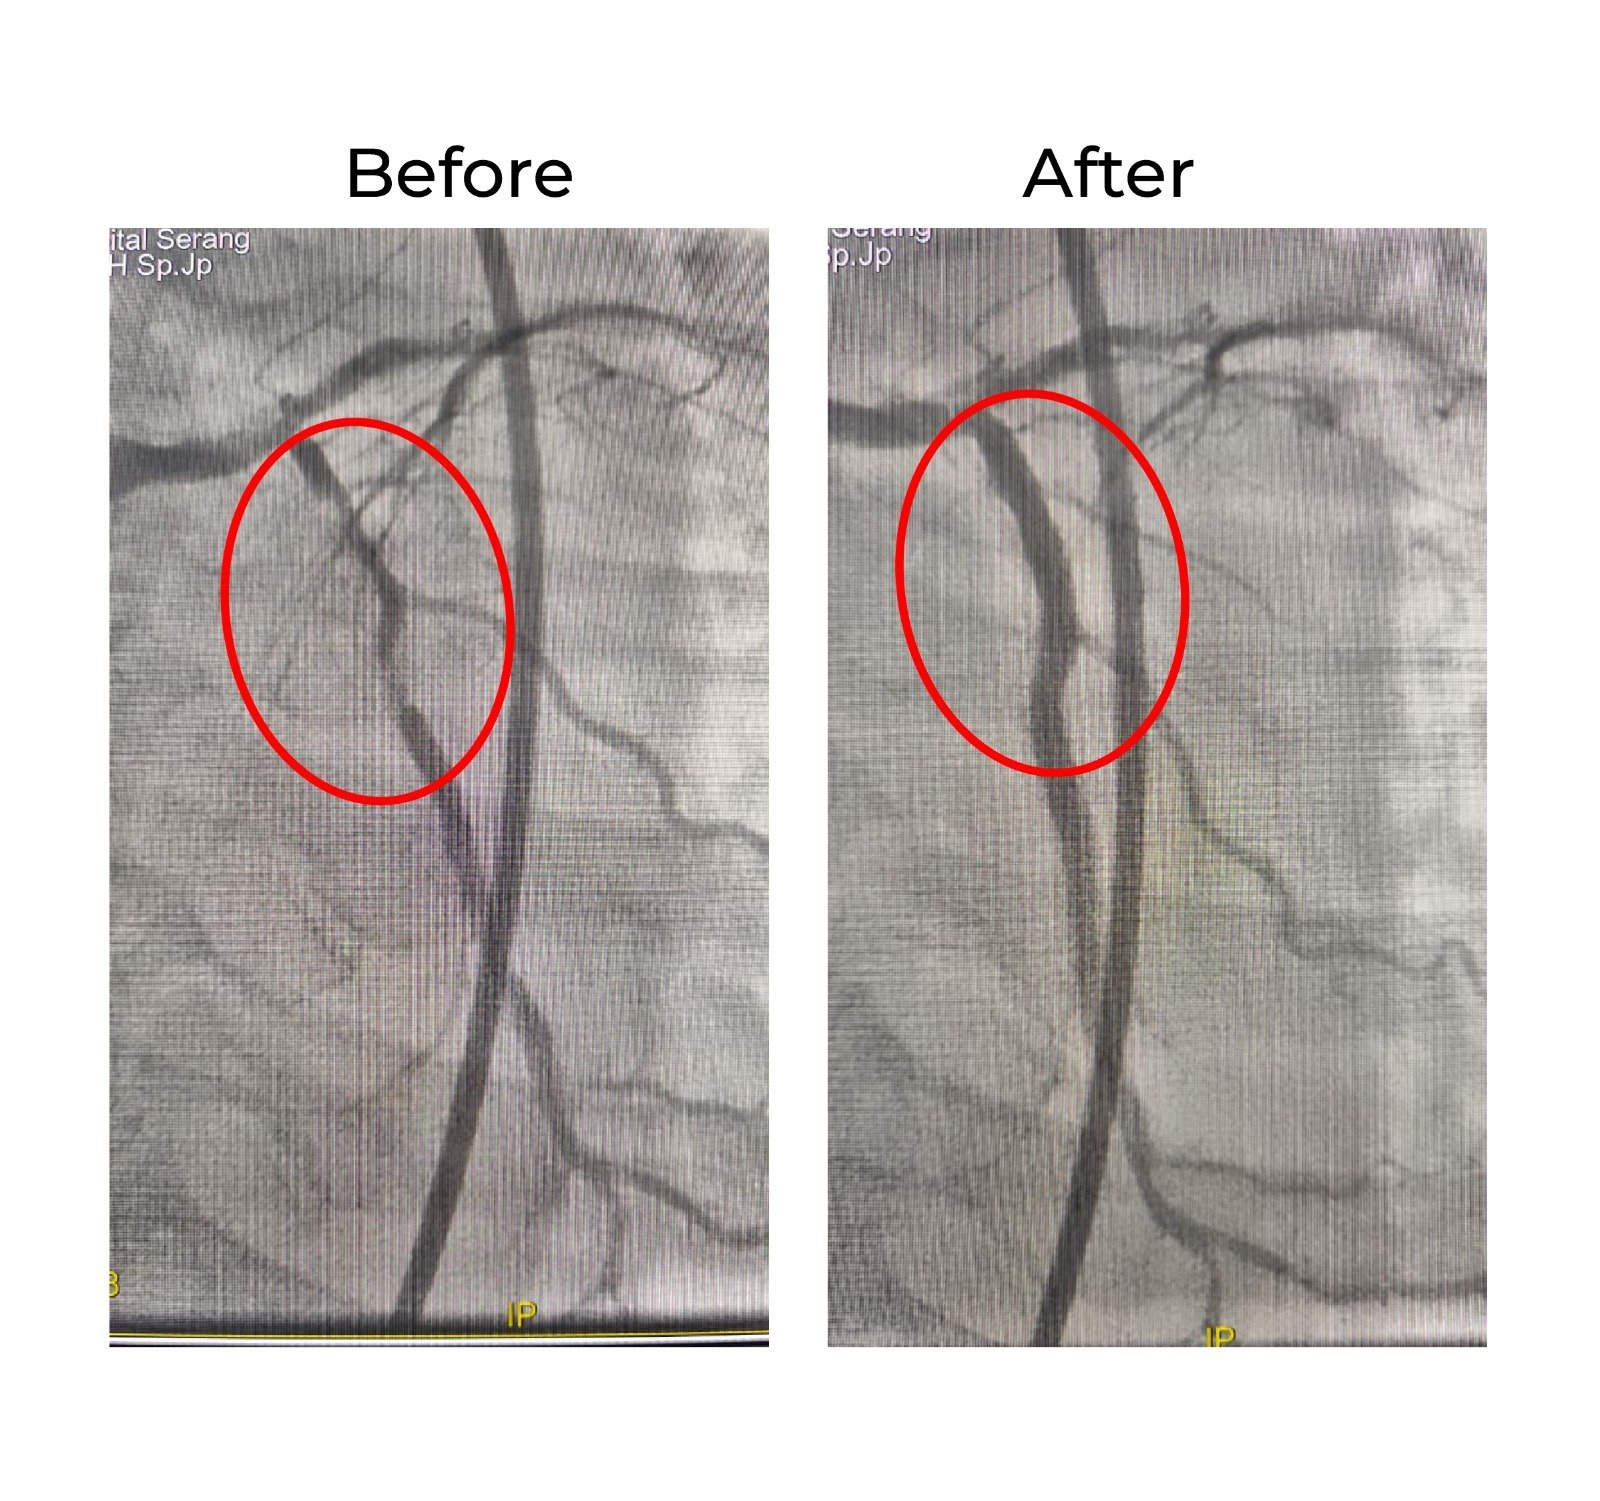

Melalui prosedur tersebut, tim dokter berhasil membuka jalan pada pembuluh darah yang tersumbat sehingga proses pemasangan stent dapat dilakukan dengan optimal.

Setelah stent terpasang, dilakukan pengembangan stent di lokasi lesi yang sebelumnya tidak dapat dilewati. Prosedur berlangsung lancar dan berhasil memperbaiki aliran darah menuju jantung.

Evaluasi lanjutan menggunakan IVUS menunjukkan hasil yang sangat baik. Ekspansi stent dinilai optimal dan aliran darah mencapai TIMI 3, yang menandakan aliran darah sudah kembali normal tanpa sisa penyempitan.